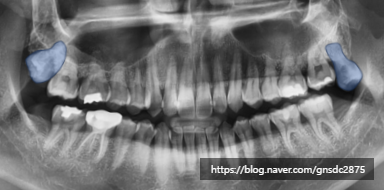

아래 사랑니만 발치하였을 경우

생길 수 있는 대표적인 문제가

바로 이 '치열'에 있습니다.

맞닿는 치아가 없는 위 사랑니는

시간이 지나며 점점 아래로 내려올 수 있고

이때 다양한 문제가 나타날 수 있습니다.